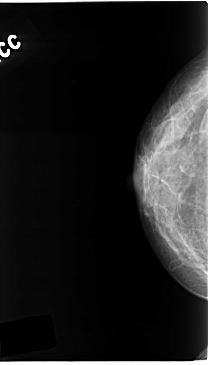

C_0134_1.LEFT_CC

LEFT_CC LINES 4728 PIXELS_PER_LINE 2776 BITS_PER_PIXEL 12 RESOLUTION 50 NON_OVERLAY